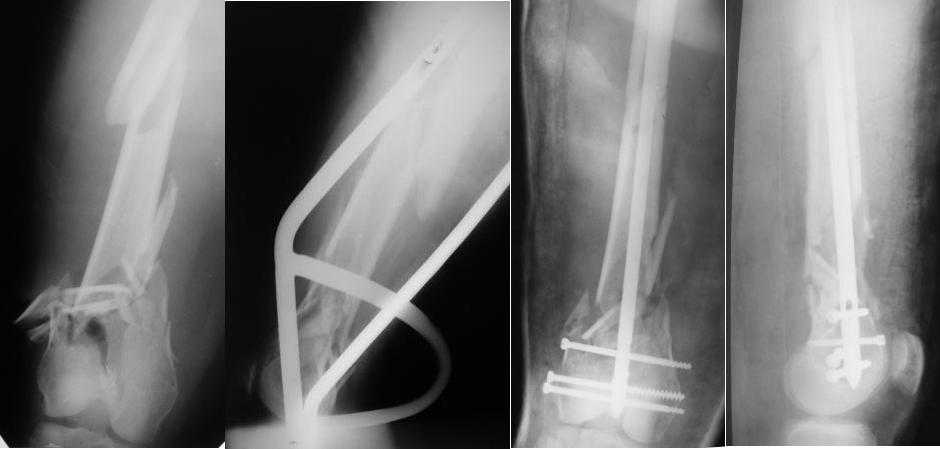

Приносим извенения за недостаток информации. Выкладываю все снимки. Стержень фирмы НПО ДЕОСТ(г.Пущино-на-оке)

Больная госпитализирована с тяжелой сочетанной травмой. Плюсом к перелому бедра имеется разрыв связок коленного сустава.

Это результат через полгода. К сожалению, пациент больше не приезжал на контрольный осмотр.

Хотя есть более приспособленные антеградные стержни для этой локализации, чем обычные диафизарные (в т.ч. как раз для этого разработан только что показанный А.Тураевым гвоздь). Но и тот, что использован, должен обеспечить хороший

результат. Еще в те времена, когда других стержней, кроме диафизарных, не

было, их успешно использовали для этой локализации. Посмотрите статью

Leung и соавт. 1991 (1,3 Mb)

На эту тему в журнале "Вестник травматологии и ортопедии им. Приорова", 2007, N3 есть наша статья "Закрытый интрамедуллярный остеосинтез с блокированием в лечении больных с переломами

дистального отдела бедренной кости".

Да и на многих отечественных и зарубежных митингах мы про эту технологию рассказывали и показывали.